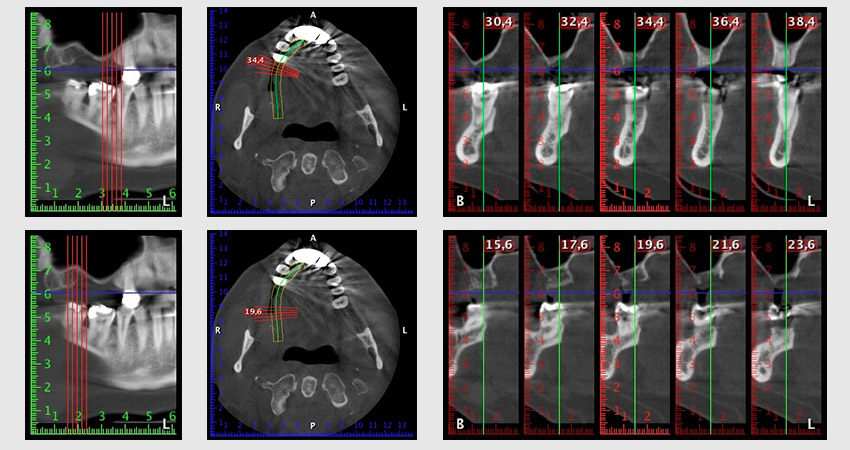

The classic incision (crestal, buccal relief) and the preparation of the mucoperiosteal flap enabled a good overview.

Sky implants (bredent) were used in this case. The surgical protocol of these, specify pilot drilling at about 1200 rpm (Fig. 9).

The following holes were drilled at a reduced speed of 300 rpm. The Implantmed demonstrated its true capability at this stage. The surgical protocol can be preset – the various positions can be selected simply by pressing the “P” position of the foot control (Fig. 10 to 11).

Inclined drilling

Image 10: Inclined drilling to dorso-cranial at 300 rpm.